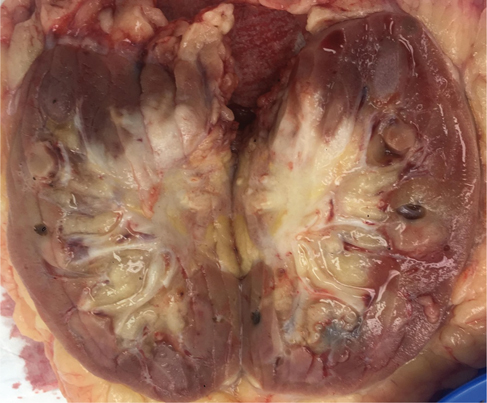

He was referred to a urology team on the suspicion of urothelial carcinoma. The urology team performed right-sided cystoscopy and retrograde pyelogram with lavage cytology which demonstrated a normal collecting system and normal urothelial cells which made the differential diagnosis of urothelial malignancy unlikely. The differential diagnosis included renal cell carcinoma (RCC). He had no haematuria; urine microscopy, culture and sensitivity were normal, and there were no other urological symptoms. The opinion of the interventional radiologist was that a percutaneous biopsy of the mass was too risky given its proximity to major vasculature structures. The patient underwent a positron emission tomography–magnetic resonance imaging (PET-MRI) scan that demonstrated a right-sided renal hilar mass encasing the renal vessels and showed evidence of invasion into the inferior vena cava (IVC) with possible invasion of the right crus of the diaphragm. No metastatic lesions were detected at other sites (Figure 1).

Fig 1

Figure 1. Coronal PET-MRI scan demonstrating a solitary enhancing lesion in the right renal hilum (arrow).